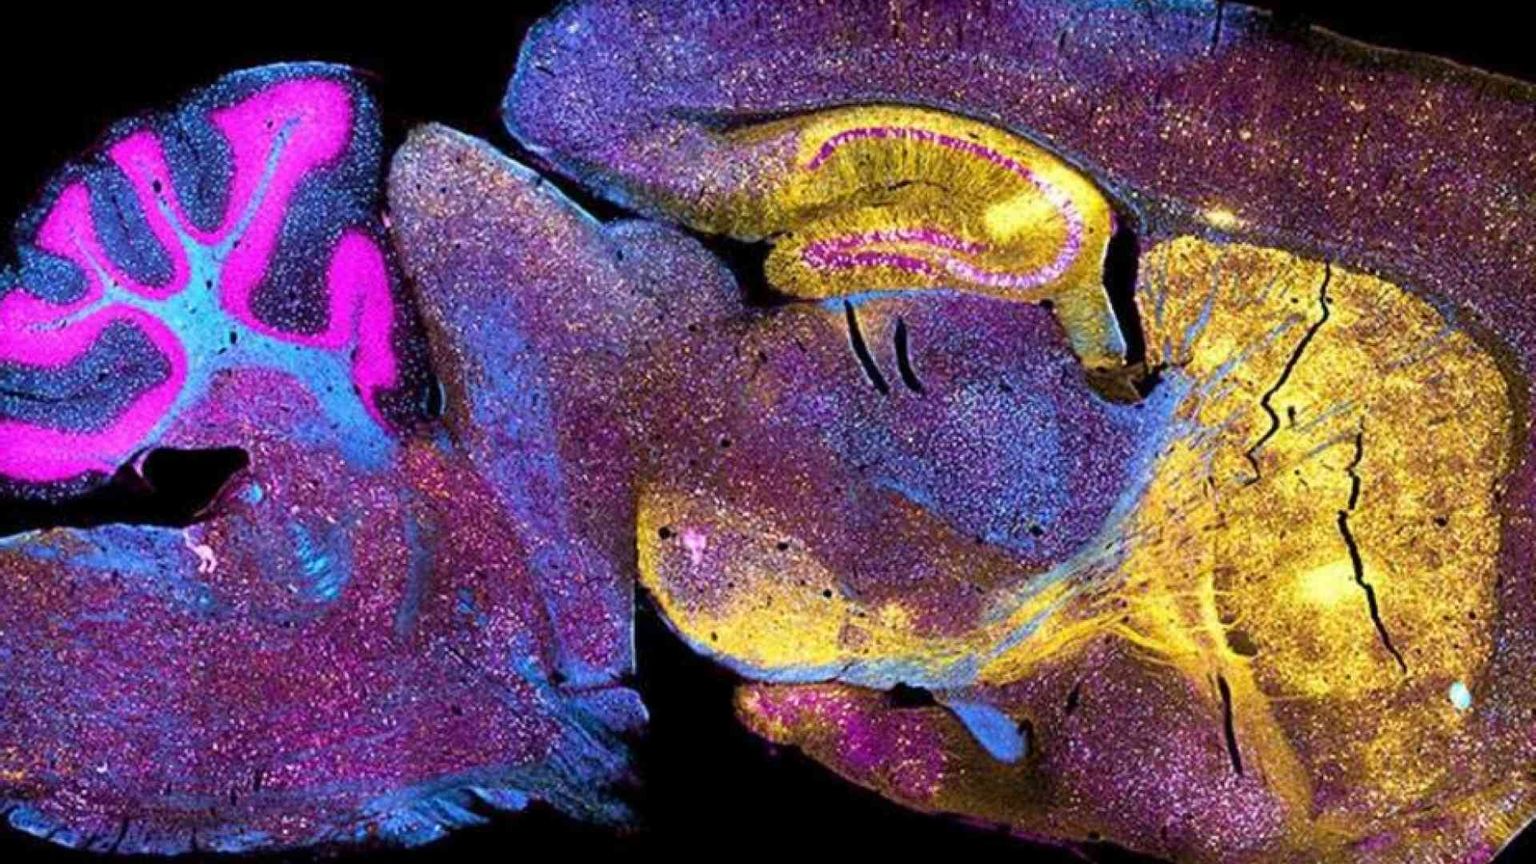

Una delle frontiere più promettenti ma anche più dibattute dal punto di vista etico è quella che coinvolge gli organoidi cerebrali. Si tratta di modelli tridimensionali dell’encefalo fatti crescere in laboratorio (per la prima volta nel 2013), fino alla dimensione di alcuni millimetri di diametro. Dopo alcuni mesi, questi “mini-cervelli” riproducono con una discreta approssimazione i diversi tipi di cellule nervose e l’architettura dell’encefalo. Ma non sviluppano i vasi sanguigni né gli apparati sensoriali. Ciò ne abbrevia la vita e li limita come modelli di ricerca.

Di qui l’idea di impiantarli in topi e scimmie, per fare sviluppare la vascolarizzazione e verificare la potenziale integrazione con le cellule del ricevente. I primi tentativi hanno dato buoni risultati, dimostrando che le cellule umane possono prosperare nel nuovo ambiente e sopravvivere per l’intera esistenza dell’animale. Dal gruppo di Sergiu Pasca, a Stanford, uno dei più attivi in questo settore, si segnala ora che organoidi cerebrali umani inseriti nella corteccia somato-sensoriale del cervello di un topo appena nato sono maturati e divenuti parte integrante dei circuiti neuronali deputati a ricevere ed elaborare informazioni sull’ambiente. E sono arrivati a costituire oltre il 15% dei tessuti complessivi.